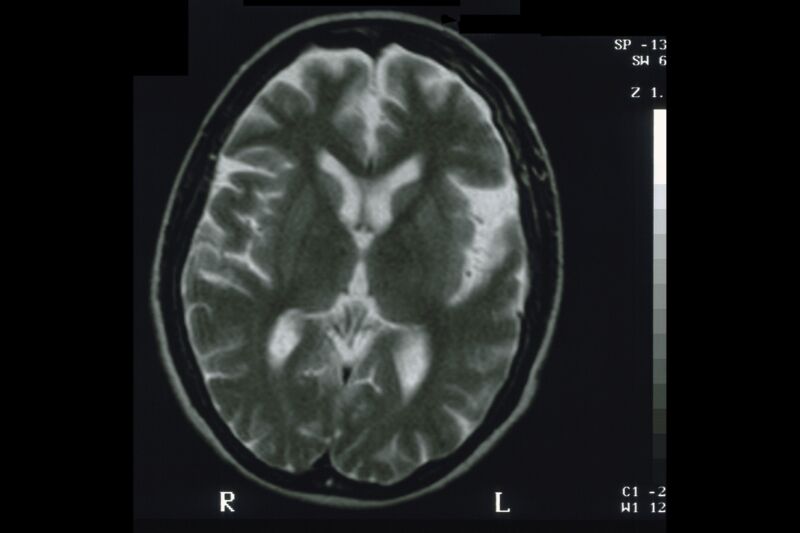

MRI of a human brain.

Enlarge / MRI of a human brain. (credit: Getty | BSIP)